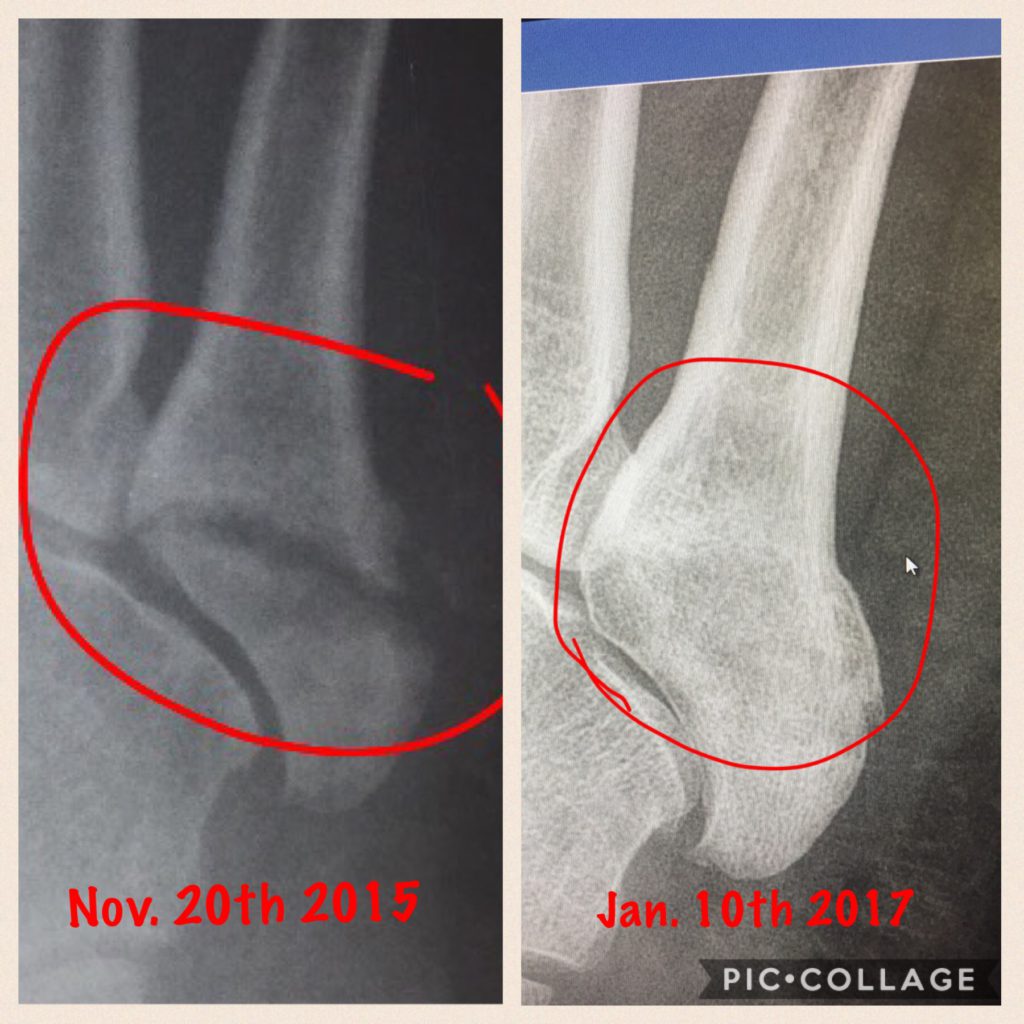

Broken Foot (Foot Fracture)

I broke three metatarsals in my left foot during my high school football season and Dr. Levine got me back in time for lacrosse in the spring. Thanks to the treatment at HSS, my foot feels better than ever and I had one of my best high school lacrosse seasons. Thanks HSS!